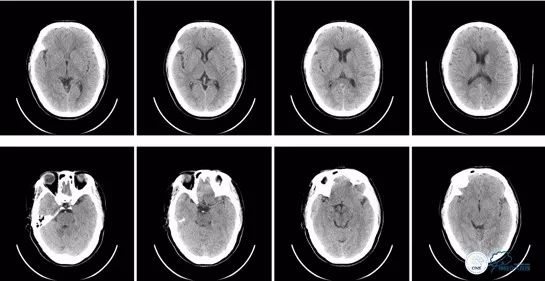

入院时急查头颅CT示:颅脑未见明显异常。ASPECT评分10分。

入院时急诊头颅CT:

图1